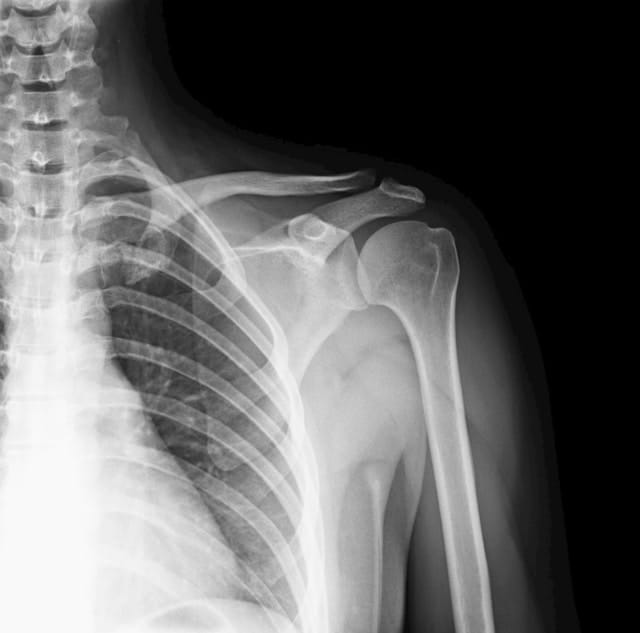

Imaging (if needed)

If required, imaging may be used:

-

X-rays to rule out fractures or joint changes

Ultrasound for soft tissue injuries